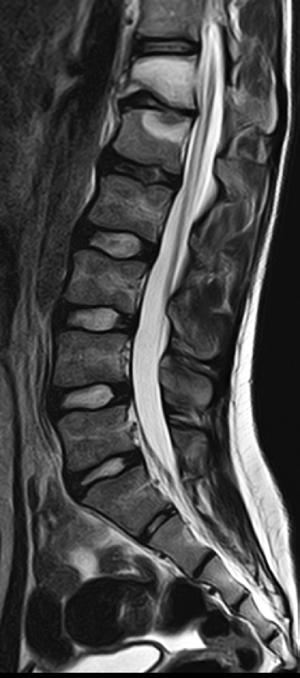

Lumbar Spine T1

Atlas SPEEDER Spine, AiCE + Compressed SPEEDER, Res: 0.35 x 0.35 mm, Scan time: 0:59 min.

Lumbar Spine T2

Atlas SPEEDER Spine, AiCE + Compressed SPEEDER, Res: 0.3 x 0.3 mm, Scan time: 0:57 min.

Lumbar Spine

- Sagital T2

- Resolution: 1.0 x 1.0 mm

- Slice Thickness: 3.5 mm